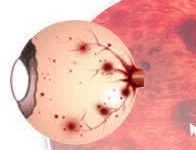

Datorită câmpului vizual mare utilizarea lentilelor fundus FL1-FL3 cel mai informativ în cazul în care există o vastă în domeniu și vystoyaniya modificări patologice, cum ar fi dezlipire de retină, tumori, retinopatie diabetică, tromboza vaselor retiniene, distrofie periferice, etc.

Retiniana hemoragia - vasele sanguine în producția unuia dintre straturi ale retinei: stratul fibrelor nervoase, straturile de mijloc ale retinei între stratul de fibre nervoase si membrana sticlos (hemoragie preretinal), între straturile de pigment și neuroepiteliul retiniene (hemoragie subretinian).

Citește mai mult.